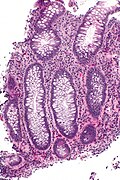

Paneth cell metaplasia. H&E stain.

The Paneth cell is characteristic of the small intestine. It is also normal in the cecum, ascending colon and transverse colon.

• Paneth cells should not be in the left colon.[1]

• If you see 'em there it is Paneth cell metaplasia.

Features:

• Supranuclear eosinophilic granules.

DDx:

• Enterochromaffin cells (AKA Kulchitsky cells).

• Subnuclear eosinophilic granules.

• Intraepithelial eosinophils.

• Eosinophils have smaller (~1/2) more intensely red granules.